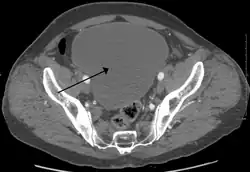

As seen on axial CT